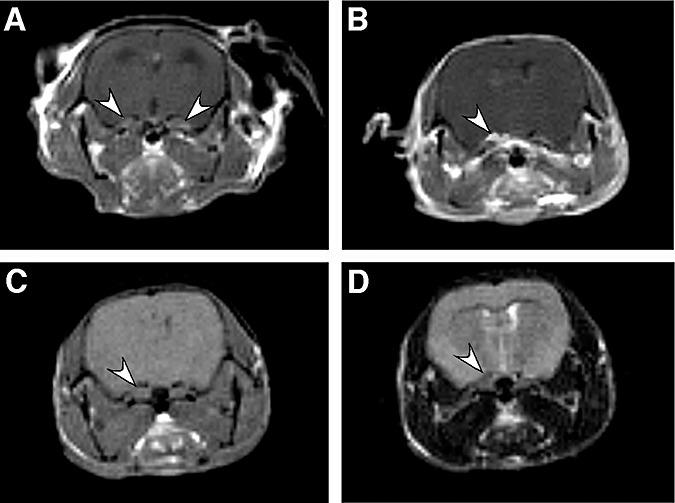

Meningiomas account for approximately 30% of all primary central nervous system tumors and are found in half of neurofibromatosis type 2 patients often causing significant morbidity. Although most meningiomas are benign, 10% are classified as atypical or anaplastic, displaying aggressive clinical behavior. Biallelic inactivation of the neurofibromatosis 2 (NF2) tumor suppressor is associated with meningioma formation in all NF2 patients and 60% of sporadic meningiomas. Deletion of the p16(INK4a)/p14(ARF) locus is found in both benign and malignant meningiomas, while mutation of the p53 tumor suppressor gene is uncommon. Previously, we inactivated Nf2 in homozygous conditional knockout mice by adenoviral Cre delivery and showed that Nf2 loss in arachnoid cells is rate-limiting for meningioma formation. Here, we report that additional nullizygosity for p16(Ink4a) increases the frequency of meningioma and meningothelial proliferation in these mice without modifying the tumor grade. In addition, by using magnetic resonance imaging (MRI) to screen a large cohort of mutant mice, we were able to detect meningothelial proliferation and meningioma development opening the way to future studies in which therapeutic interventions can be tested as preclinical assessment of their potential clinical application.